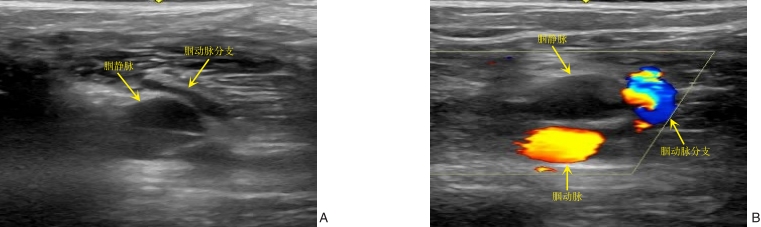

图3 超声显示腘静脉周围可能围绕着腘动脉分支 A:超声2D图像显示腘静脉周围存在小血管,有明显搏动;B:彩色多普勒超声显示腘静脉周围存在腘动脉分支Fig.3 Ultrasound showing the branches of the popliteal artery possibly wrapping around the popliteal vein A: Ultrasonic 2D image showing small vessels around the popliteal vein with evident pulsation; B: Color Doppler ultrasound showing the branches of the popliteal artery around the popliteal vein